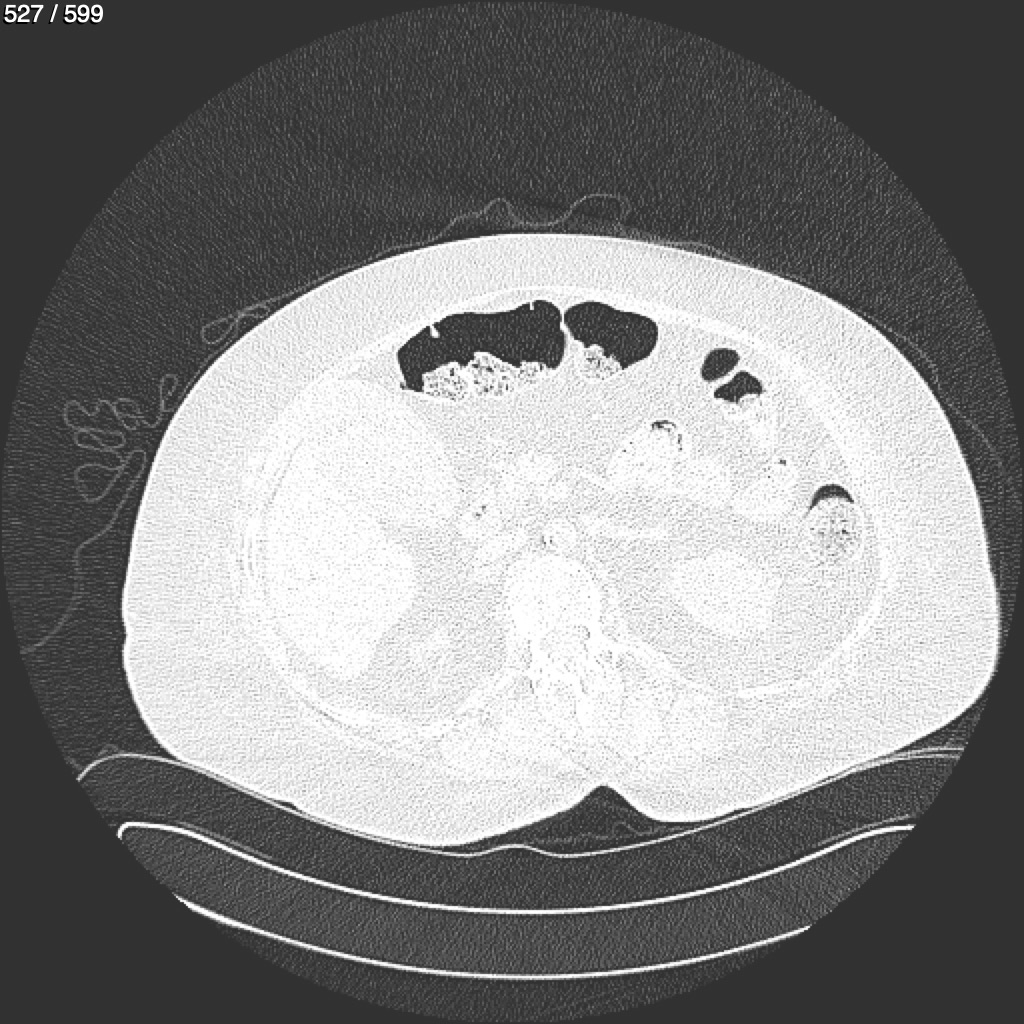

Home G​l​o​r​i​a​ ​G​l​a​d​y​s​ ​B​e​a​s​l​e​y​ ​-​ ​T​ó​r​a​x​ ​T​o​r​a​x​_​S​i​m​p​l​e​ ​(​A​d​u​l​t​o​)